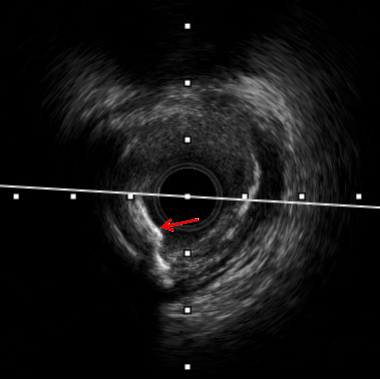

术中IVUS检查提示患者左回旋支近远段多处偏心钙化及钙化小结,钙化较重,导致多种介入器械难以通过,因此启动Shockwave冲击波球囊技术方案。

术前

超过180度钙化环

钙化结节